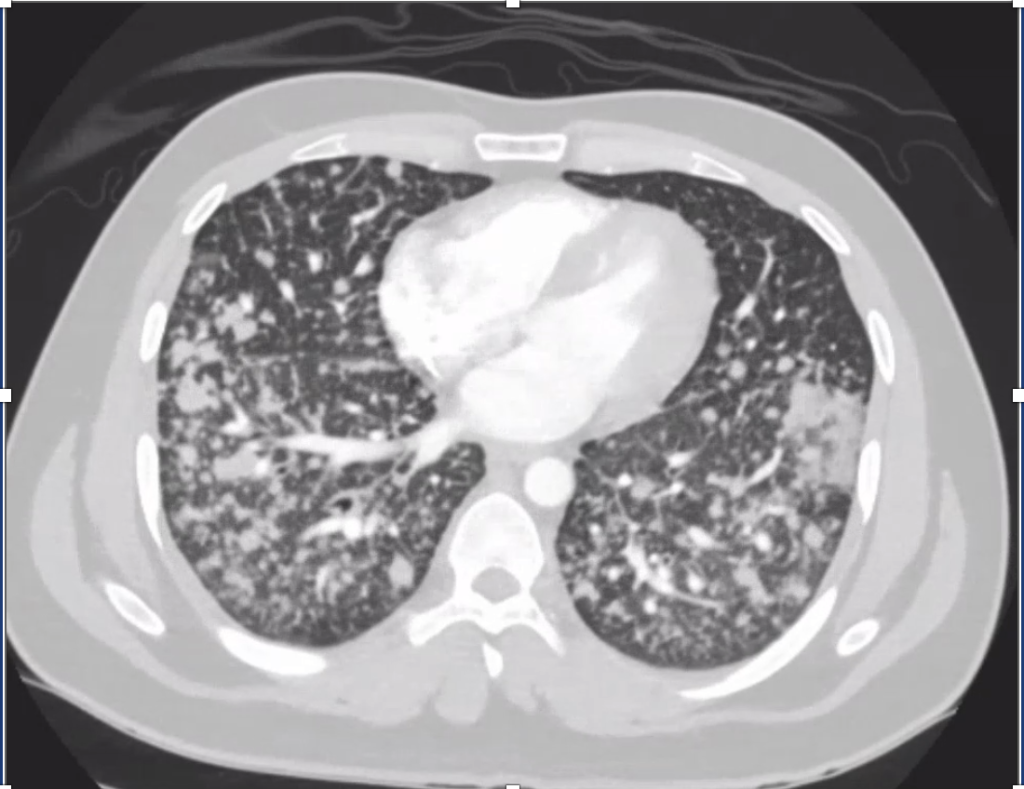

2) Imaging pearls—nodular pattern recognition

• Ask three things: craniocaudal distribution, symmetry, central vs peripheral.

• Centrilobular (spares pleura/fissures): airway-centered (e.g., NTM, bronchiolitis, tree-in-bud).

• Perilymphatic (tracks fissures/pleura & septa): sarcoid, lymphangitic spread.

• Random/diffuse (involves pleural surfaces): hematogenous spread → think miliary TB, disseminated fungal, septic emboli, metastatic disease.

• Interval change matters: new cavitation and confluence can upweight infection or aggressive malignancy.

• Path: TTF-1+, CK7+, napsin A → pulmonary adenocarcinoma with a fusion driver.

• Therapy: Targeted TKI (crizotinib) → dramatic radiographic response of miliary lung disease and CNS lesions.

• Teaching point: even “miliary TB-like” lungs + CNS lesions in a 20-something can be driver-positive lung cancer—don’t let age or pattern blind you.